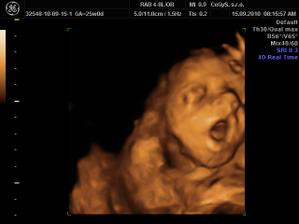

Náš anjelik🙂